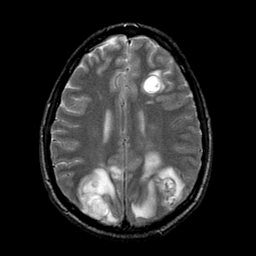

Sarcoma, MR Study #1 mr-t2 -- Slice #16

[Home][Help][Clinical] Slice 16